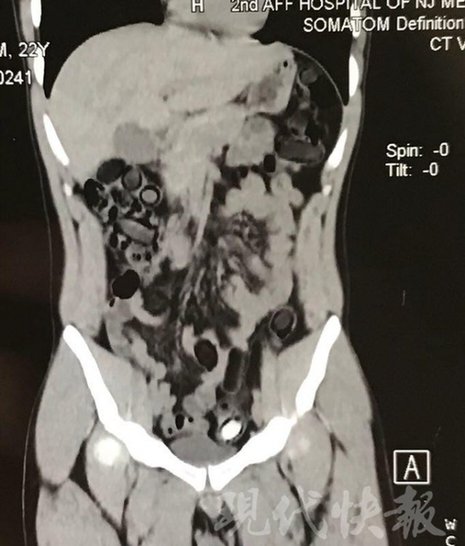

小伙體內(nèi)藏毒300余克 CT掃描圖密密麻麻

運毒小伙:希望被判處死刑

由于毒品在體內(nèi)一旦泄露有可能致命,警方第一時間將阿永帶到醫(yī)院進(jìn)行檢查。CT 掃描的結(jié)果顯示,阿永體內(nèi)布滿了密密麻麻的白色圓柱狀固體,就像一粒粒的蠶蛹。在南京市公安局鼓樓分局二板橋派出所,阿永分四次排出了毒品,毛重369.99克。經(jīng)訊問,阿永交代了自己全部的犯罪事實。目前,阿永已被刑事拘留。